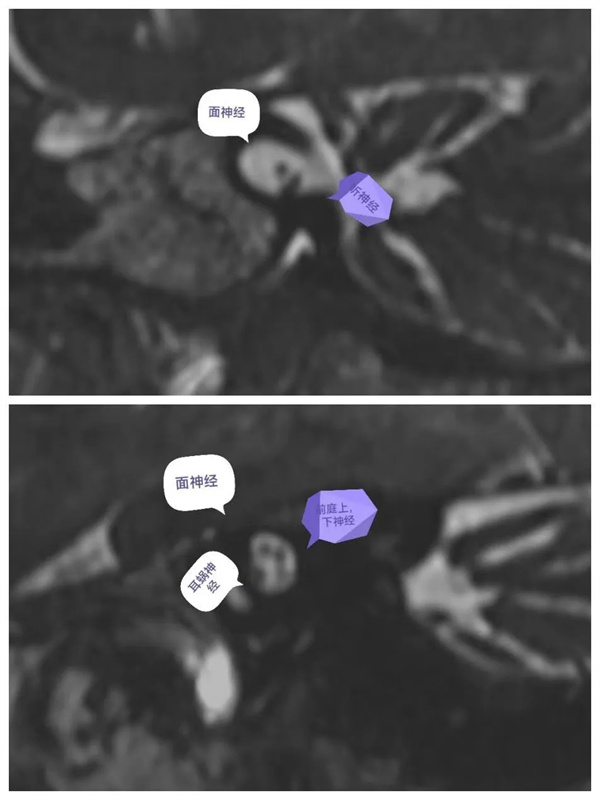

圖4:神經(jīng)軸位顯示面聽神經(jīng)走形及分支,面神經(jīng)(前上)、耳蝸神經(jīng)(前下)、前庭上神經(jīng)(后上)、前庭下神經(jīng)(后下)。